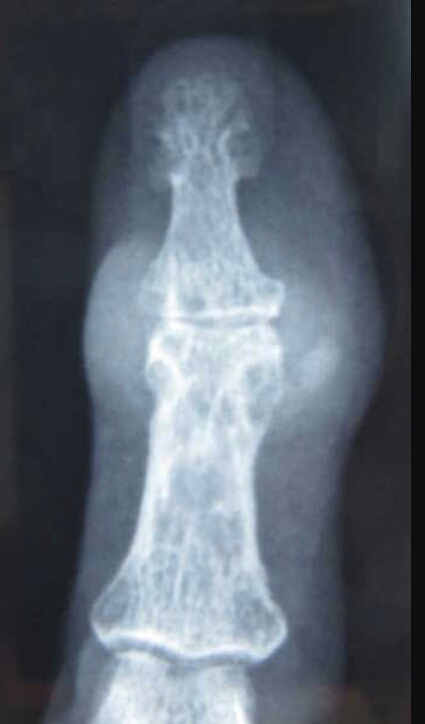

Name the feature on the xray.

Heberden’s node